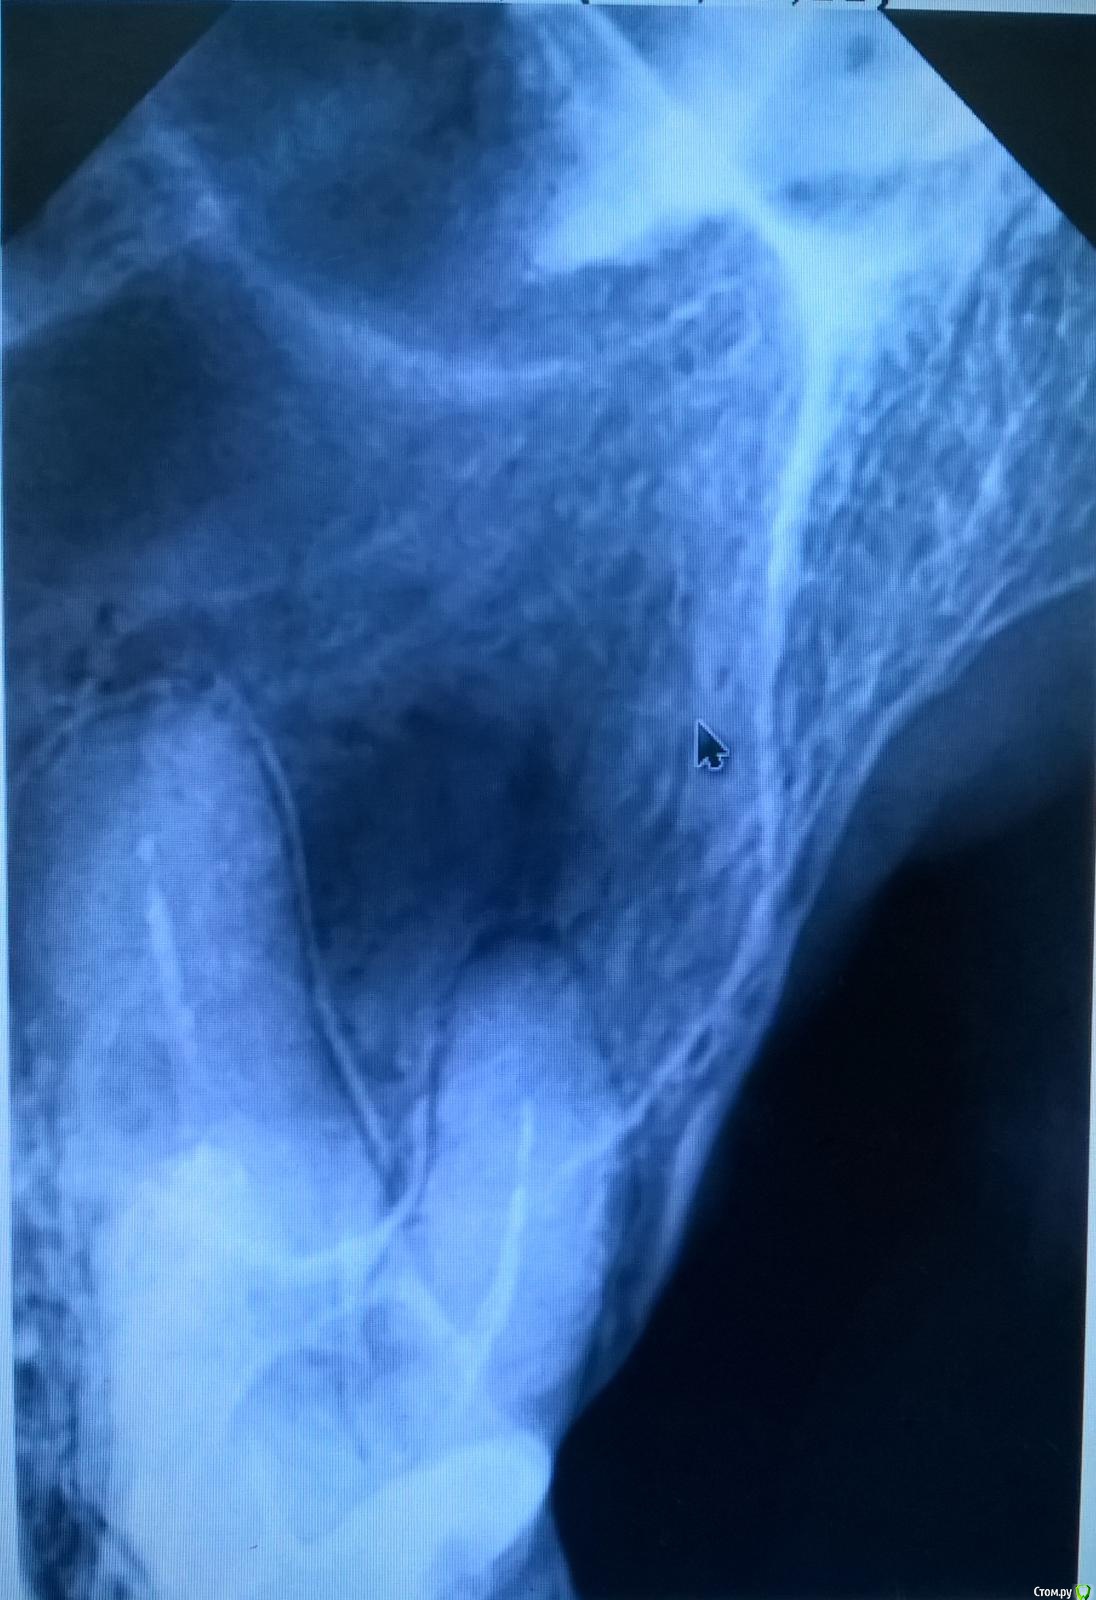

Дней 5-6 назад у меня на одном зубе (номер 25 или 26) слетела коронка, поначалу она шаталась дней 5,а  потом слетела, зуб (или точнее, его остатки) не болит вообще.

Вчера ходил в частную зубную поликлинику. Они сделали снимок, и посмотрев на него, не смогли определить, можно ли ставить коронку снова или нет. Поскольку, по их словам, между корнями зубов, возможно, образовалось некое плохое образование (возможно, киста или что-то ещё), и по сему, они точно не уверены, что нужно делать, либо лечить, либо ещё что-то делать.

Смотревшие сей снимок врачи не уверены, посоветовали спросить у ещё кого-то, либо сделать компьютерное 3D моделирование (но это дополнительные рублей тыща).